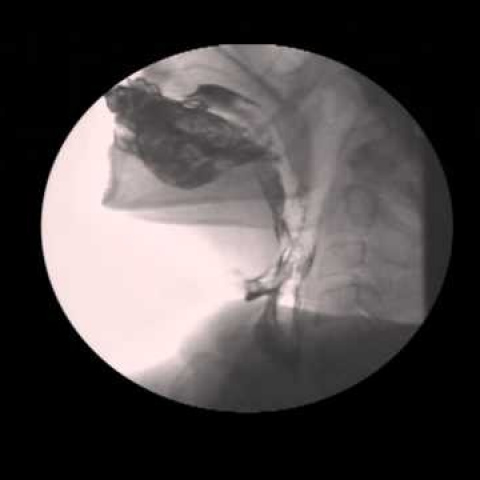

Faringograma y esofagograma con cine o video (estudio de deglucion). 874910 Idime (2022)

INCLUYE MEDIO DE CONTRASTE